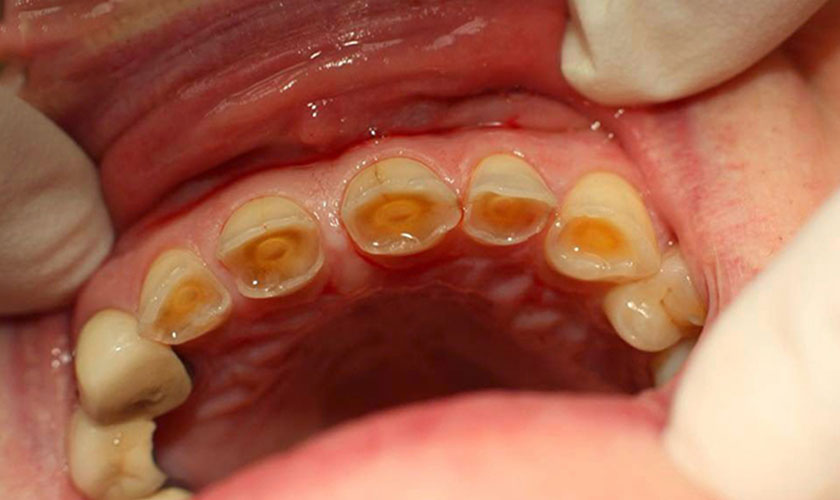

Mòn răng là tình trạng men răng bị mất dần theo thời gian do tác động cơ học hoặc hóa học. Khi men răng bị mòn, lớp ngà răng bên trong lộ ra khiến răng trở nên ê buốt, nhạy cảm, dễ sứt mẻ và giảm tuổi thọ răng.

Đáng lưu ý, men răng không có khả năng tự tái tạo, vì vậy mòn răng nếu không được phát hiện sớm sẽ tiến triển nặng dần và khó điều trị hơn.

Răng ngắn lại, bề mặt nhẵn, mất các gờ tự nhiên

Răng dễ sứt mẻ, đổi màu vàng sậm do lộ ngà răng